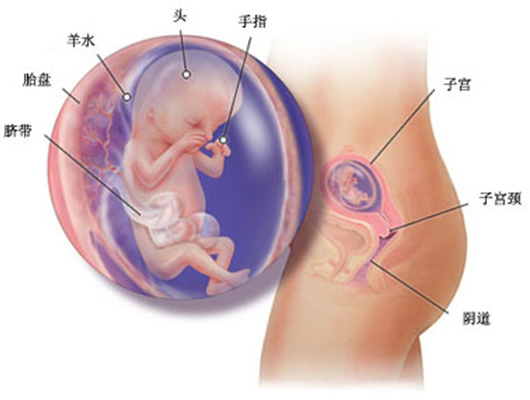

怀孕第 14 周胎儿发育情况

胎儿现在已经 76-100 毫米,重达 28 克。在他(她)手指上已经出现独一无二的指纹印。

如果胎儿是个女孩子,她的卵巢里现在大约有 200 万个卵,出生时就仅存 100 万个了,等她长大时,会越来越少,到 17 岁时可能仅剩 20 多万个。